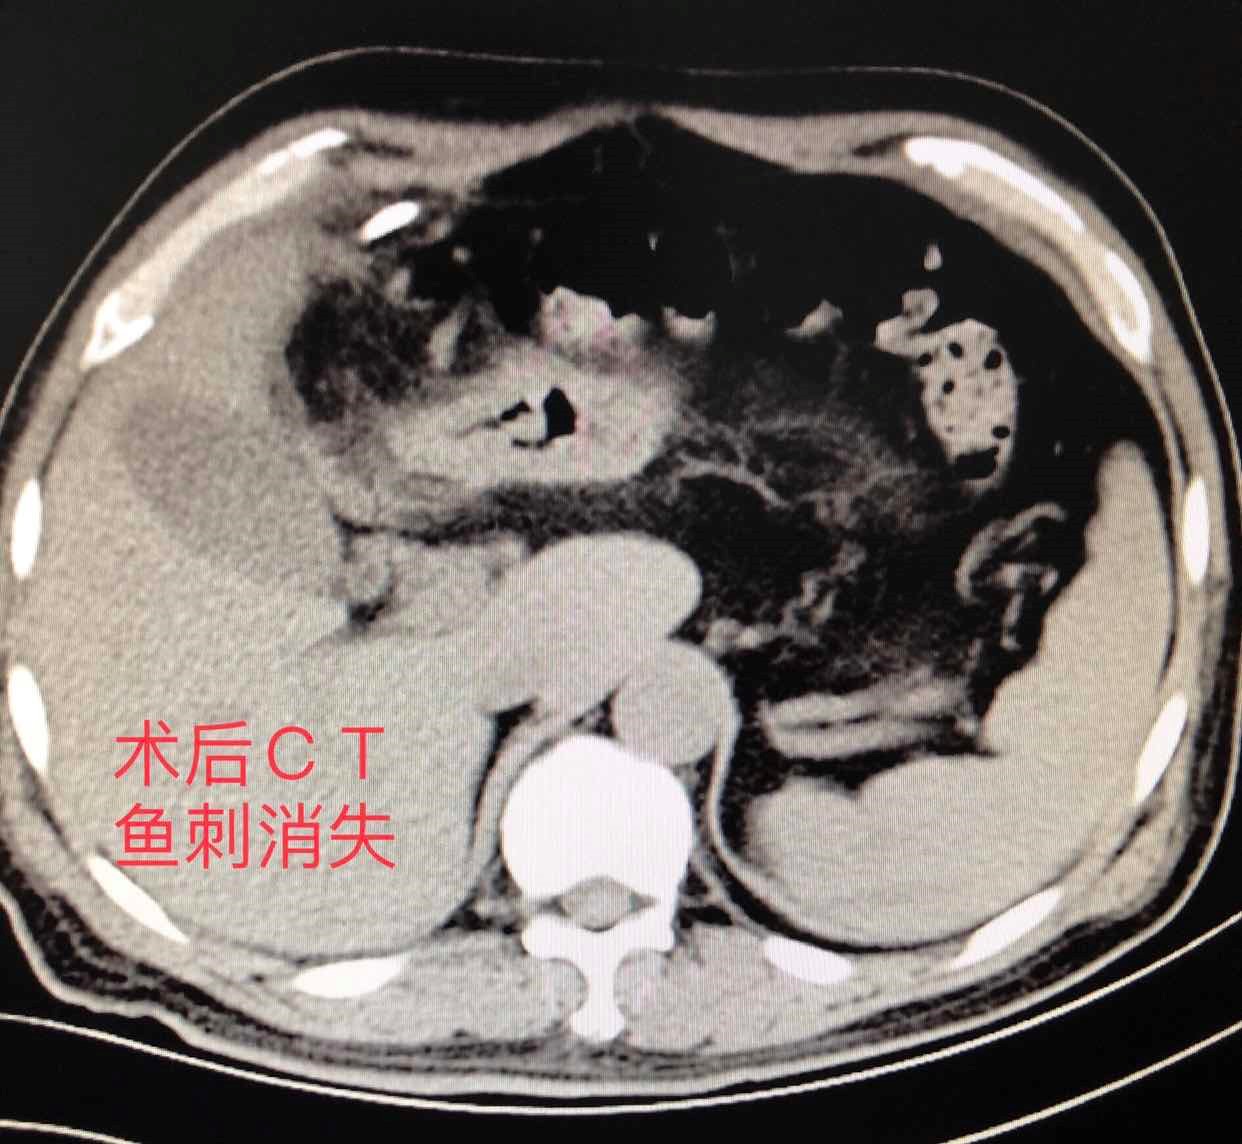

患者主要症状为肝脓肿导致的感染发热,先行超声引导下肝脓肿穿刺置管引流。引流后患者体温恢复正常,复查CT显示脓肿体积缩小。“鱼刺”位置未发生变化,决定行腹腔镜下探查取出“鱼刺”。术中经仔细分离后,将鱼刺完整取出。术后测量鱼刺长约4cm,与术前CT检查显示一致。